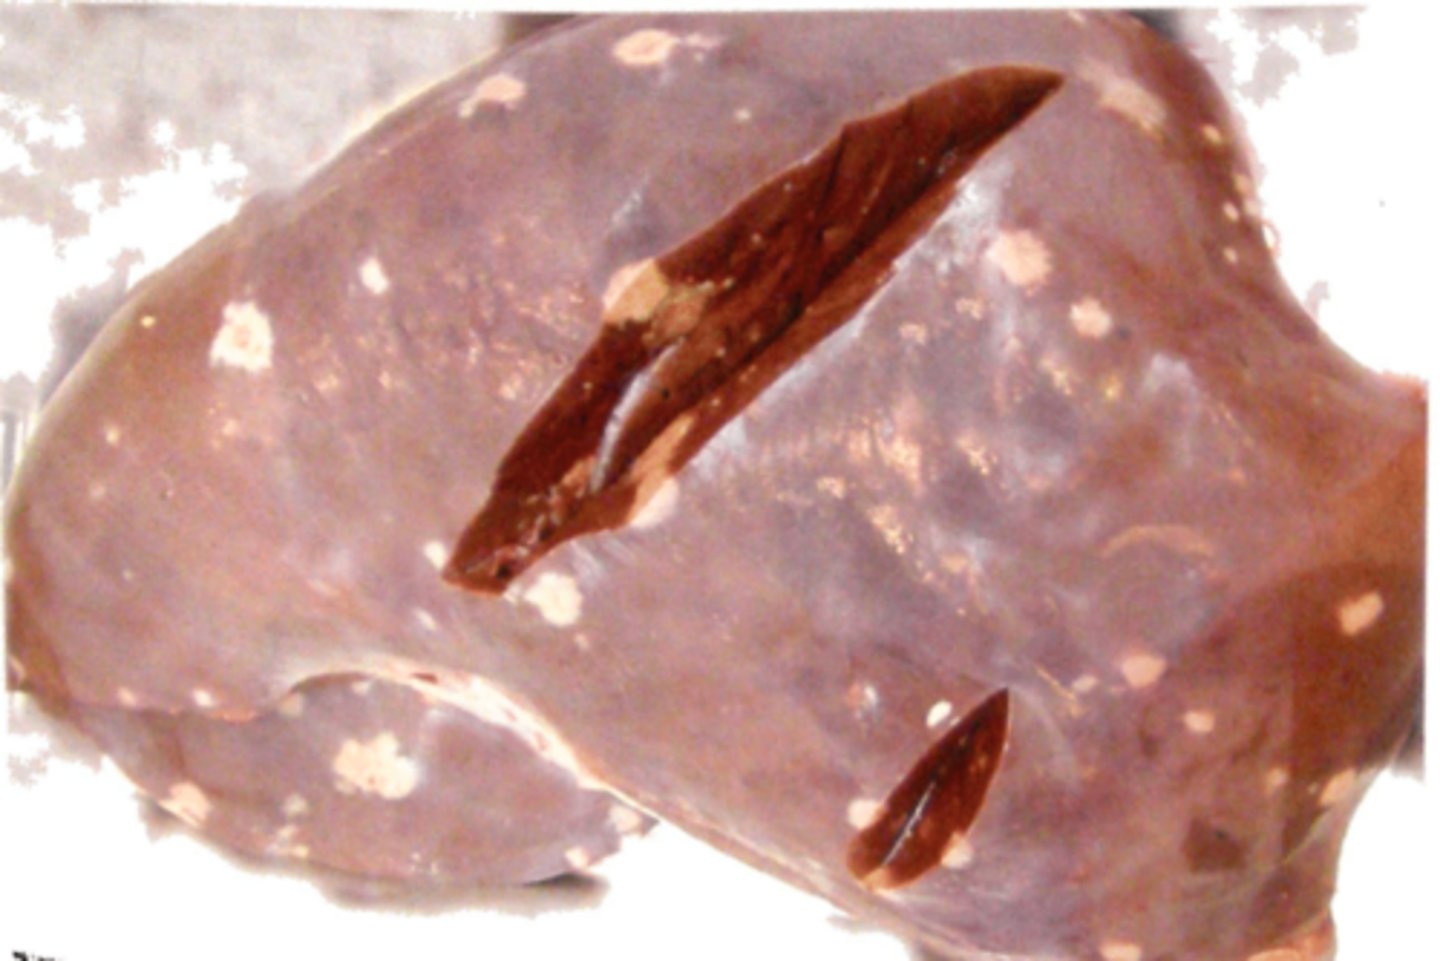

Kronisk multifokal, fibrøs, interstitiel hepatitis

Ætiologi: migration af Ascaris suum larver

Lever fra svin, hvad er den patoanatomiske diagnose og ætiologien?

Kronisk multifokal, fibrøs, interstitiel hepatitis

Ætiologi: migration af Ascaris suum larver

Lever fra svin, hvad er den patoanatomiske diagnose og ætiologien?